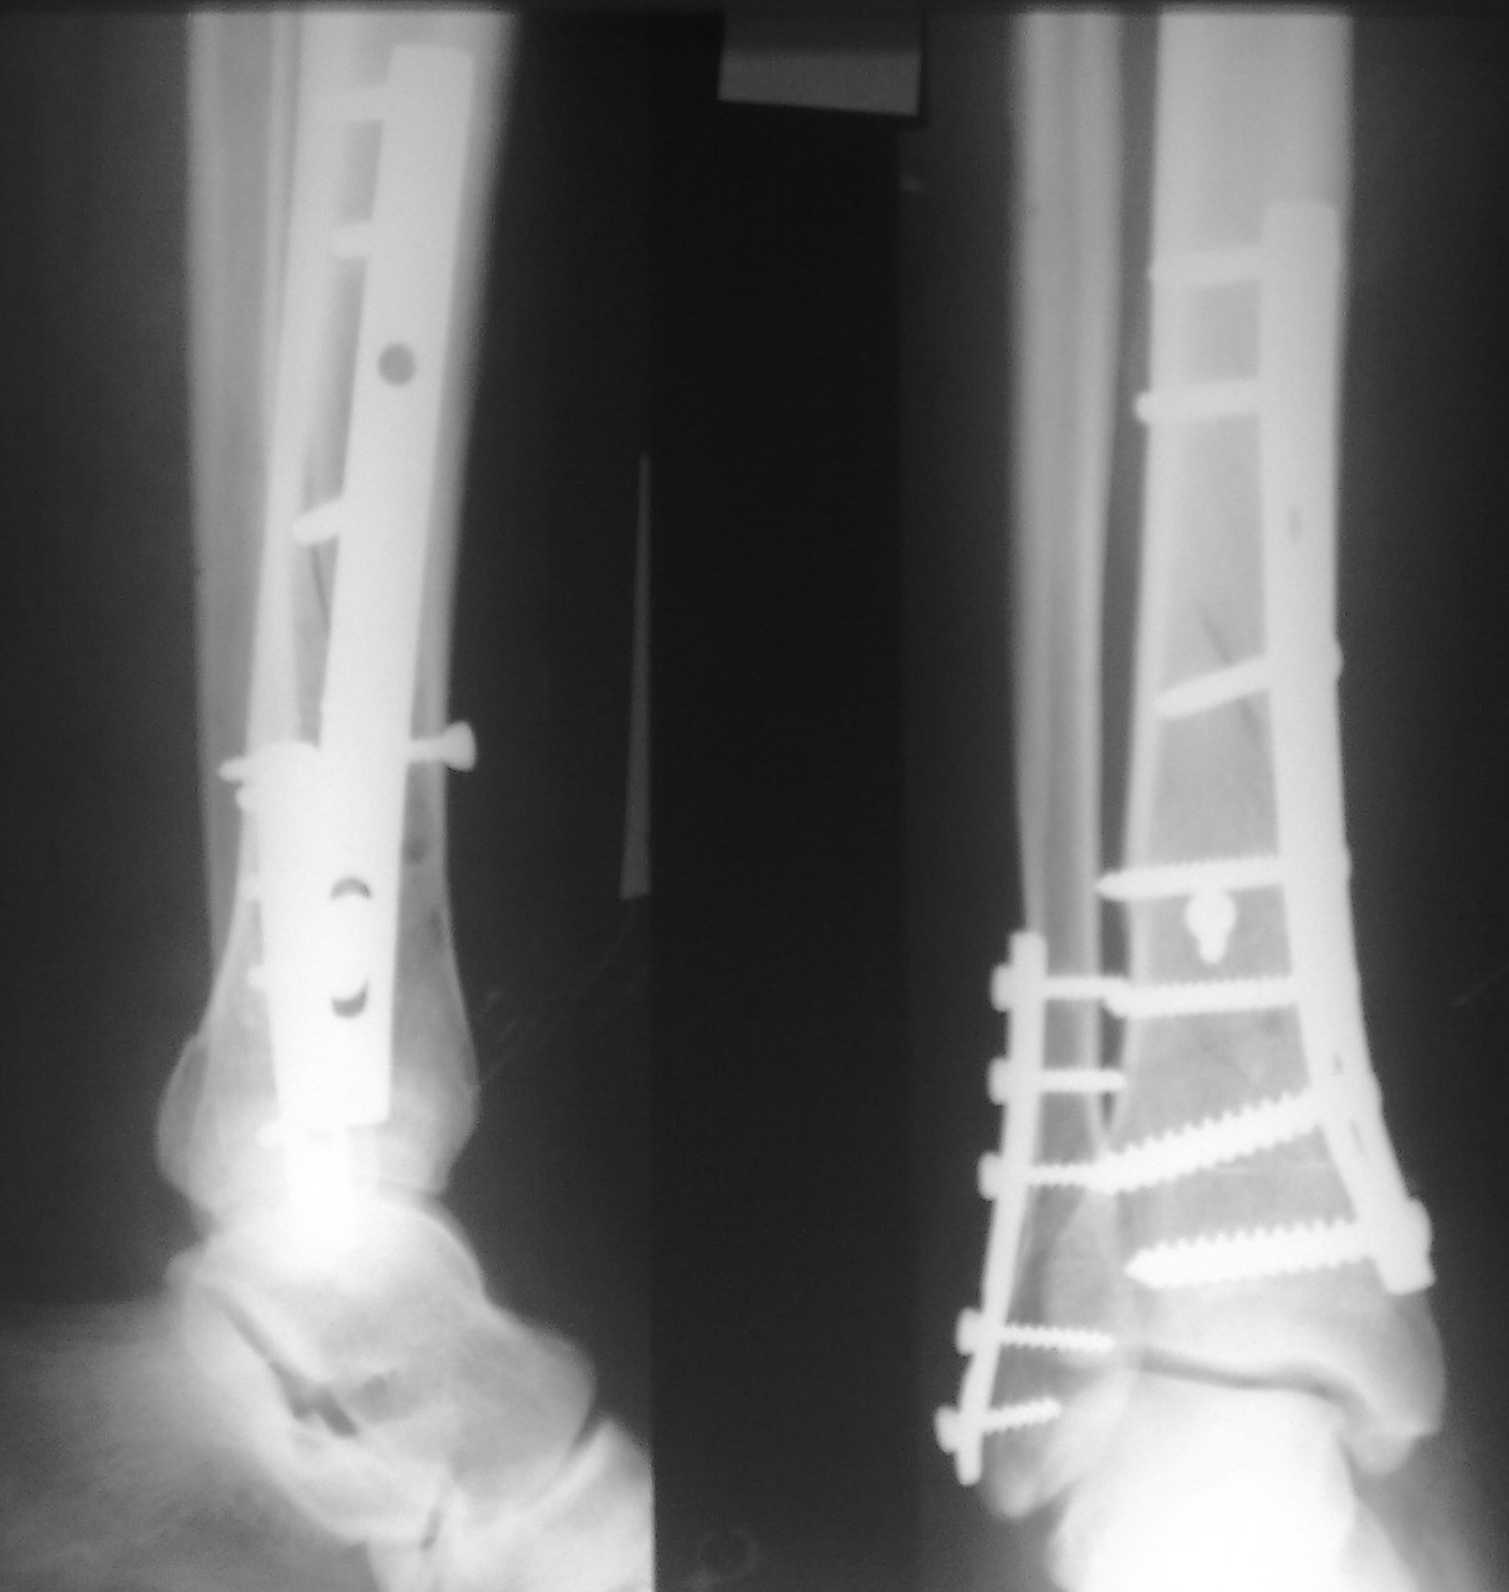

Перелом большой берцовой кости - серьезное повреждение, сопровождающееся болезненными ощущениями и нарушением функции ноги. На этой странице вы найдете много фотографий, позволяющих вам более детально изучить эту травму.

Чрескостный остеосинтез лодыжки

Остеосинтез двухлодыжечного перелома

Медицинские изображения

Здесь представлены медицинские изображения переломов большой берцовой кости, сделанные врачами в процессе диагностики и лечения. Вы сможете увидеть, как выглядит этот тип травмы на рентгеновских снимках и других медицинских изображениях.